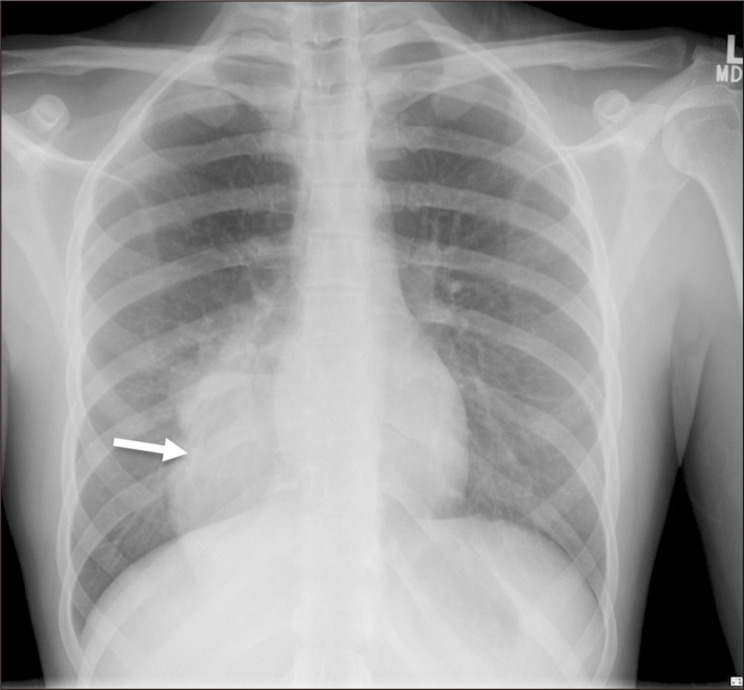

一位20岁出头的患者表现为咳嗽和炎症标志物升高。胸片显示右下区异常混浊。随后的计算机断层扫描显示右下叶脓肿,由主动脉产生的异常血管供血。这些发现与肺泡内隔离合并脓肿形成一致。患者接受抗生素治疗后出院,并计划在心胸外科医生的护理下进行选择性栓塞和肺叶切除术。一项文献综述显示,关于肺隔离的工作有限,很少有涉及类似表现的病例报告。因此,我们的病例是文献中罕见而重要的补充。

A patient in her early 20s presented with a cough and elevated inflammatory markers. A chest radiograph revealed an abnormal opacity in the right lower zone. Subsequent computed tomography showed an abscess in the right lower lobe that was fed by an anomalous vessel arising from the aorta. These findings were consistent with intralobar sequestration complicated by abscess formation. The patient was treated with antibiotics and discharged home, with plans for elective embolization and lobectomy under the care of the cardiothoracic surgeons. A literature review revealed a limited body of work on pulmonary sequestrations, with very few reported cases involving similar presentations. Thus, our case represents a rare and important addition to the literature.